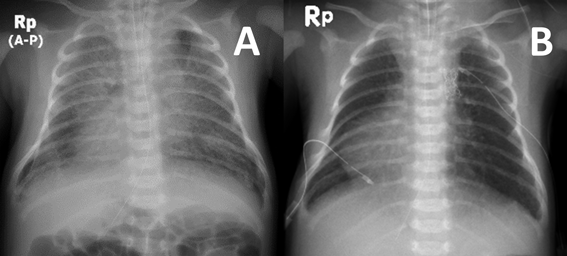

総肺静脈還流異常を合併した垂直静脈狭窄に対するステント留置中のバルーンエントラップメントEntrapment of a Balloon Catheter during Stent Implantation for Vertical Venous Stenosis in Two Neonates with Single Ventricle and Total Anomalous Pulmonary Venous Connection